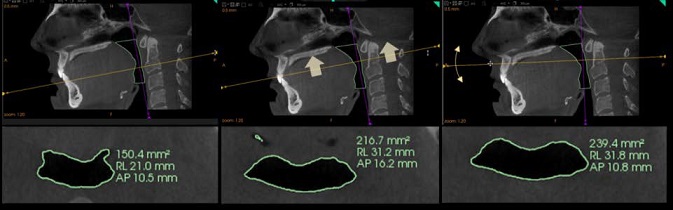

Lo strumento Airway segmentation (Segmentazione via aerea) permette agli utenti di segmentare la via aerea anche con solo due clic. La segmentazione è visualizzata in tempo reale durante la produzione dei tracciati della via aerea ed il risultato è visibile immediatamente nelle visualizzazioni sia della scena 3D sia MPR.

Misurazioni dinamiche

Le misurazioni di qualsiasi sezione nel piano assiale sono visualizzate automaticamente e aggiornate in modo dinamico mentre l'utente naviga con la sezione.